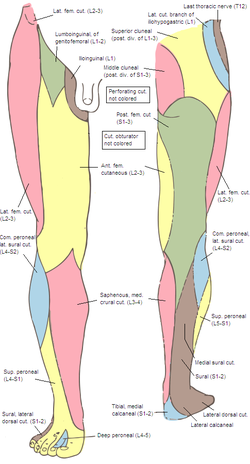

origin and course of superior cluneal nerve

posterior rami of L1-L3 nerves

crosses iliac crest

origin course and distribution of saphenous nerve

spinal cord level

O femoral nerve

C descends with femoral vessels through femoral triangle and adductor canal then descends with great saphenous vein

D supplies skin on medial side of leg and foot

L3-L4

name the clunial nerves and their distribution

spinal cord levels

superior (posterior rami of L1-L3), inferior (S2-S3) and middle clunial nerves (posterior rami of (S1-S3)

supplies the skin of the gluteal region as far as greater trochanter

origin and course of middle clunial nerve

posterior rami of S1-S3 nerves

exits through posterior sacral foramina and enters gluteal region

origin and course of inferior clunial nerve

posterior cutaneous nerve of thigh

curves around inferior border of gluteus maximus

origin course and distribution of sural nerve

O formed by the union of the cutaneous banches from the tibial and common fibular nerves

C descends between heads of gastroc; becomes superficial at middle of leg; descends with small saphenous vein; passes inferior to lateral malleoulus to lateral side of foot

origin course and distribution of lateral femoral cutaneous nerve

O L2-L3

C emerges from the lateral border of the psoas major, crosses the iliacus muscle obliquely toward ASIS. Under the inguinal ligament, over sartorius muscle into the thigh, where it divides into an anterior and a posterior branch.

D lateral skin of thigh

origin course and distribution of posterior cutaneous nerve of the thigh

O S1-S3

C From pelvis below piriformis, beneath gluteus maxius and back of thigh, bakc of knee and dives into deep fasica and runs with small saph to middle of back of leg. gives off inferior clunial n.

D posterior surface of thigh and leg, skin of perineum